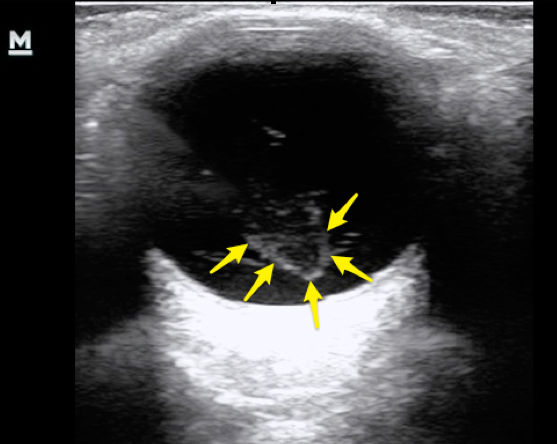

4. Retinal Detachment: Sudden, spontaneous "flasher and floaters" or "spots or stars" or loss of vision that is like a "curtain closing." Usually loss of peripheral vision. Risk factors: recent eye injury or surgery, severe nearsightedness (think elderly). ED Role: POCUS - look for a delicate floating line in the anechoic eyeball space. If their is no macular separation, their vision can be saved! This is an optho emergency. Unless you're Errel, err on the side of caution and call optho for all of these since we might not be able to definitively determine if the macula is involved.

5. Vitreous Hemorrhage and Posterior Vitreous Detachment: Floaters, strings, or cobwebs in their vision that change with eye movement. Flashes of light. Risk factors: retinal damage (surgery, trauma, prior retinal tear), Diabetic Retinopathy, trauma, sickle. ED role: POCUS: swirling cloud-like opacity at moves with ocular movement and is not tethered to the optic disk or retina "washing machine sign". ED role: Avoid Anticoagulation, elevate head of bed, optho referral.